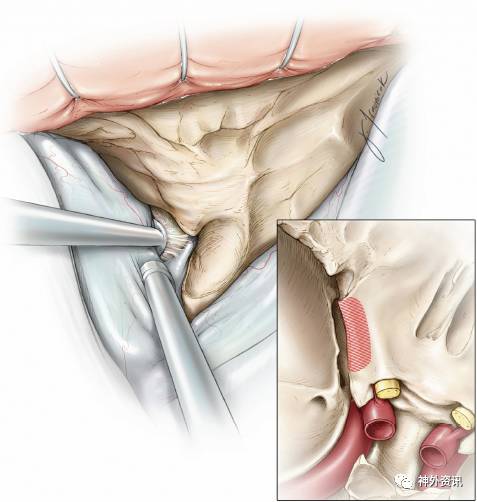

图11. 充分抬起蝶骨嵴内侧部硬脑膜之后,进一步分离便受到一膜性结构的限制,该结构即为眶上裂处的外侧额颞硬膜返折(lateral frontotemporal dural fold),也称为眶颞骨膜返折(orbitotemporal periosteal fold),其包含有脑膜眶带(meningoortbital band)(见插图)。笔者切开此带约5mm,随后即在蝶骨嵴附近沿眶上裂将颞窝硬脑膜从海绵窦外侧壁上钝性剥离开。通过这一关键步骤,可进入颞窝硬脑膜和覆盖于眶上裂的结缔薄膜之间的间隙。

切开眶颞骨膜返折,即可显露眶脑膜动脉,将其电凝后切断。泪腺神经位于该间隙内;海绵窦内的其他颅神经都位于泪腺神经内侧。因此,切开眶颞骨膜返折不可超过5mm。腰穿脑脊液引流可避免对额颞叶使用固定牵开器。